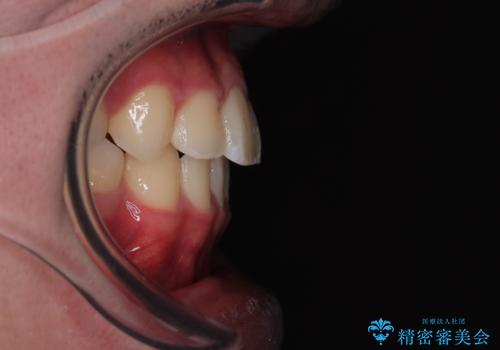

- 前歯のデコボコと口元の突出感を気にして来院された患者様です。

上下前歯がくちばしのように突出していたため、上下左右の第一小臼歯4本を抜歯し、ワイヤー装置にて矯正治療を行うこととしました。

左上は第二小臼歯が90度捻れており、状態が良くない歯であったため、左のみ第二小臼歯を抜歯することとしました。

上顎骨に対して下顎骨がやや前方位に位置しているため、下顎前歯をあまり内側に移動させることができず、口元の突出感改善は期待以上にはならないと予測しておりましたが、満足いくの引っ込み具合となりました。